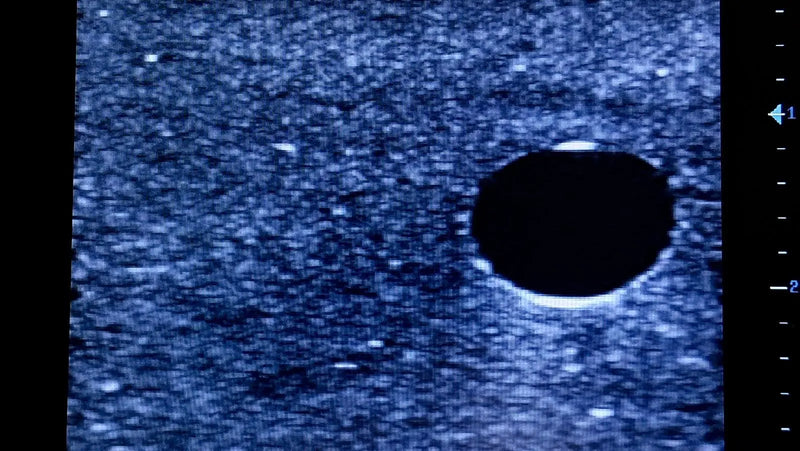

Thiết bị huấn luyện đơn giản, mạnh mẽ cho phép luyện tập lặp đi lặp lại kỹ thuật xâm nhập dưới hướng dẫn siêu âm một cách thực tế, giúp nâng cao thành thạo máy siêu âm, khéo léo sử dụng đầu dò và nhận biết cấu trúc giải phẫu. Tất cả chỉ với việc chuẩn bị và bảo trì tối thiểu.

Máy huấn luyện siêu âm BIOTME® mô phỏng mô người thật cả về cảm giác và đặc tính phản hồi sóng siêu âm. Vết kim sẽ biến mất sau vài ngày luyện tập, tăng cường tính chân thực và tiết kiệm chi phí.

Kích thước (Inch): 13 x 6.7 x 3.15